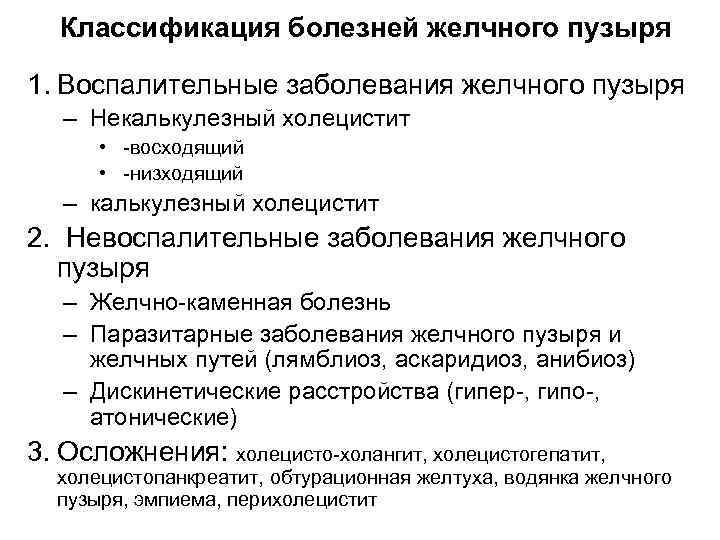

Классификация болезней желчного пузыря 1. Воспалительные заболевания желчного пузыря – Некалькулезный холецистит • -восходящий • -низходящий – калькулезный холецистит 2. Невоспалительные заболевания желчного пузыря – Желчно-каменная болезнь – Паразитарные заболевания желчного пузыря и желчных путей (лямблиоз, аскаридиоз, анибиоз) – Дискинетические расстройства (гипер-, гипо-, атонические) 3. Осложнения: холецисто-холангит, холецистогепатит, холецистопанкреатит, обтурационная желтуха, водянка желчного пузыря, эмпиема, перихолецистит

Классификация болезней желчного пузыря 1. Воспалительные заболевания желчного пузыря – Некалькулезный холецистит • -восходящий • -низходящий – калькулезный холецистит 2. Невоспалительные заболевания желчного пузыря – Желчно-каменная болезнь – Паразитарные заболевания желчного пузыря и желчных путей (лямблиоз, аскаридиоз, анибиоз) – Дискинетические расстройства (гипер-, гипо-, атонические) 3. Осложнения: холецисто-холангит, холецистогепатит, холецистопанкреатит, обтурационная желтуха, водянка желчного пузыря, эмпиема, перихолецистит